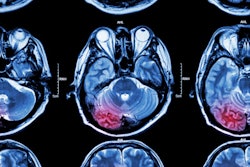

One of the big challenges in developing high-performing radiology artificial intelligence (AI) algorithms is having access to a large image dataset with high-quality labels for training. A group from Switzerland found a way around that problem while developing deep-learning models to detect clinical stroke lesions on MRI.

To increase the size of their training set, the developers used synthetic images that were produced by extracting stroke lesion features from clinical cases and then combining them with normal exams. After 40,000 of these synthetic images were added to the training dataset, an AI model was able to achieve over 90% sensitivity for detecting stroke lesions on a separate test set.